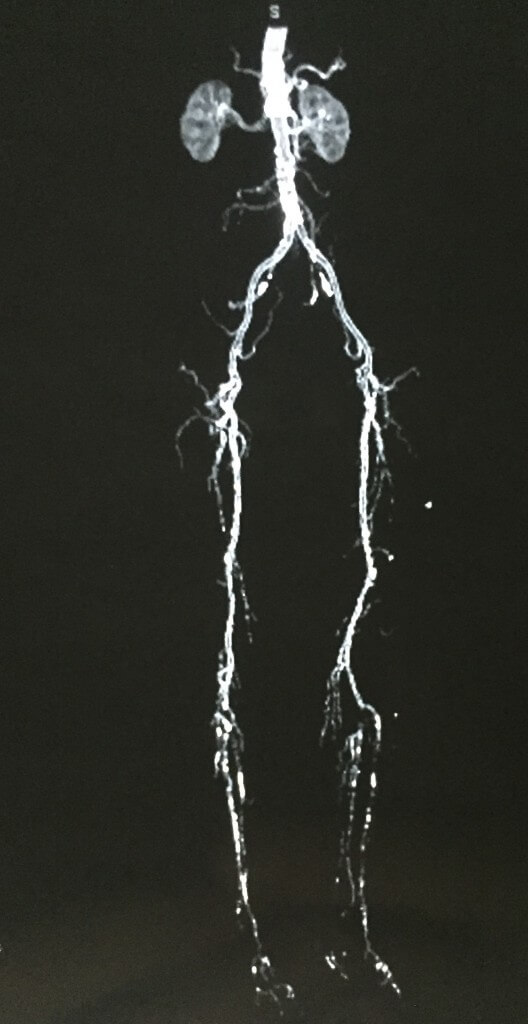

La enfermedad arterial es la principal causa de amputaciones no traumáticas…….

Sus principales causas son la diabetes y el tabaquismo.

En esta angiotomografía se observan las múltiples lesiones desde la aorta abdominal hasta distal, siendo más evidente a nivel de la arteria poplítea (a nivel de la rodilla hasta los pies).